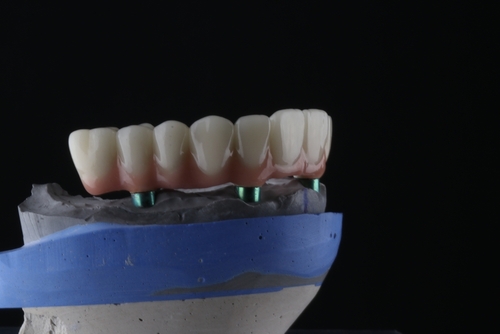

Custom Implant Crowns for Natural Aesthetics

Implants for Single, Multiple, or Full-Arch Replacement